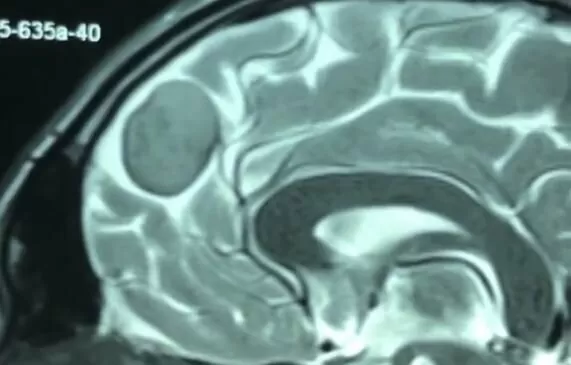

Це доброякісне новоутворення, що розвивається із оболонок головного мозку, рідше – судинних сплетінь шлуночків ГМ. Менінгіоми деформують ГМ, зміщують та стискають його структури, порушуючи їх роботу.

В залежності від локалізації, розділяють конвекситальні менінгіоми, базальні менінгіоми (передньої, середньої, задньої черепної ямки), менінгіоми серповидного відростку (фалькс-менінгіоми), менінгіоми намету мозочку. Фалькс-менінгіоми можуть мати двосторонній рост: як в праву, так і в ліву півкулі.